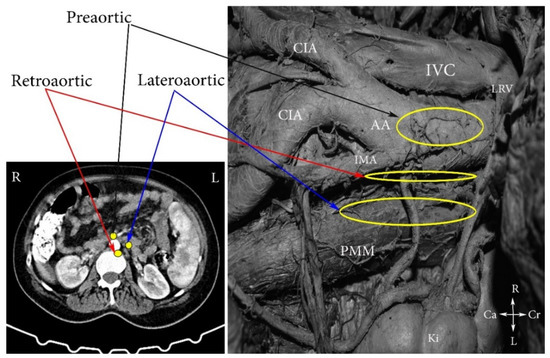

4. Regions and Their Boundaries during PALND

- (A)

- The high paraaortic (supramesenteric) region is limited: ventrally—LRV; medially—AA; laterally—ureter and Gerota fascia; dorsally—IMA; caudally—psoas major muscle.

- (B)

- The low paraaortic (inframesenteric) region is limited: ventrally by the IMA; medially—by the AA, dorsally—the left common iliac artery (CIA); laterally—the ureter and the Gerota fascia, caudally—the psoas major muscle.

- (C)

- The aortocaval or interaortocaval region (includes preaortic and precaval PALNs) is limited: ventrally—LRV, laterally—left—lateral aspect of the AA, right—lateral aspect of inferior vena cave, dorsally—AA bifurcation, caudally—prevertebral fascia, anterior longitudinal ligament and psoas major muscle.

- (D)

- The paracaval region (includes laterocaval and retrocaval PALNs) is limited: ventrally—right renal vein (RRV); dorsally—midpoint of the lateral aspect of right CIA, laterally—right ureter and right psoas major muscle, caudally—the psoas major muscle.